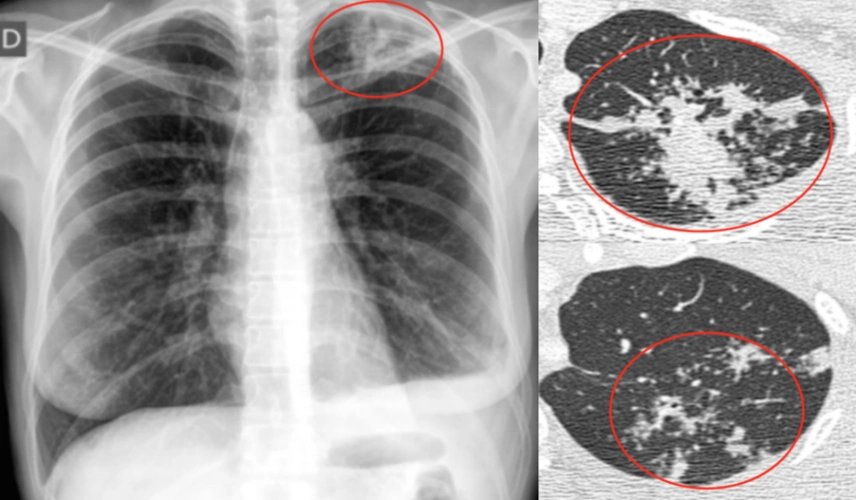

陈起航教授肺结核的影像学评价遏制终止终结肺结核2